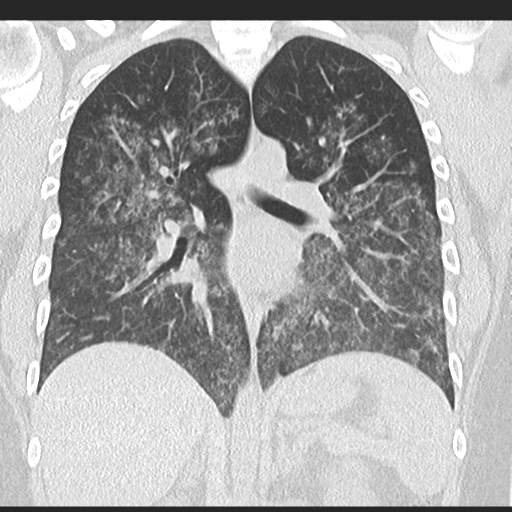

Diffuse alveolar haemorrhage due to vasculitis

Source: radiopaedia.org

- HRCT: Diffuse ground-glass opacities and alveolar consolidation.

- High-resolution CT (HRCT): Shows diffuse ground-glass opacities and hemosiderin deposition

- HRCT: Shows interstitial lung disease and ground-glass opacities